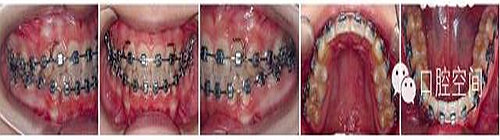

女性,11歲,表現(xiàn)為骨型Ⅱ類錯(cuò)頜畸形,高角,下頜后縮,上下牙弓前突。X線片顯示正處于生長發(fā)育高峰期。治療前面頜像及X線片見圖2。通過拔除4個(gè)第一前磨牙,應(yīng)用標(biāo)準(zhǔn)方絲弓定向力技術(shù)矯治,并在上頜第一磨牙近中植入種植體。初始弓絲上頜為0.017×0.022英寸不銹鋼方絲(1英寸=2.54 cm),下頜為0.018×0.025英寸不銹鋼方絲,佩戴高位J鉤牽引頭帽12小時(shí)/天,先牽引尖牙往遠(yuǎn)中,再換用0.020×0.028英寸和0.019×0.025英寸不銹鋼方絲分別彎制關(guān)閉曲內(nèi)收上下切牙關(guān)閉間隙,在內(nèi)收前牙的同時(shí),對上頜后牙進(jìn)行垂直向的主動(dòng)壓低。間隙關(guān)閉后應(yīng)用10-2支抗預(yù)備系統(tǒng)直立下頜后牙,上頜始終通過高位J鉤牽引頭帽進(jìn)行垂直向控制。最后下頜換用0.0215×0.028英寸全尺寸弓絲穩(wěn)定下牙列,使用Ⅱ類牽引和垂直牽引,對Ⅱ類關(guān)系進(jìn)行過矯正。治療中面頜像見圖3。通過25個(gè)月的矯治,拆除矯治器,制作佩戴保持器。治療后FMA減少了1°,F(xiàn)MIA和Z角均接近正常值(表3),下頜骨垂直向生長明顯,治療后面型明顯改善,咬合關(guān)系良好。治療后面頜像及X線片見圖4,治療前后頭影測量對比圖見圖5。

圖3典型病例治療中面像